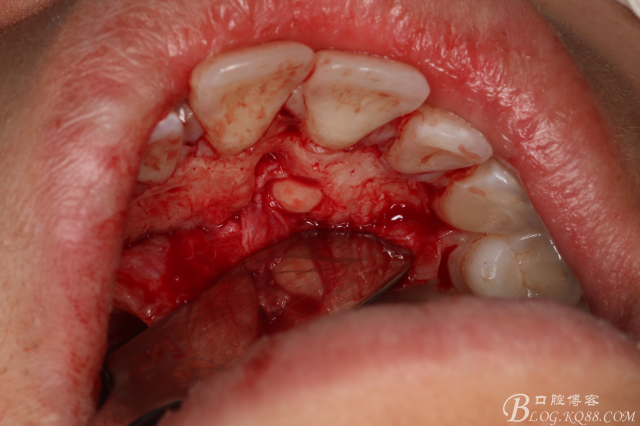

圖7.翻瓣

圖8.翻瓣暴露出鼻腭神經(jīng)管及腭側(cè)骨面

圖9.在切牙管旁邊去骨、暴露出21根尖區(qū)多生牙牙根

圖10.繼續(xù)去骨、發(fā)現(xiàn)多生牙部分位于鼻腭管內(nèi)

圖11、微創(chuàng)牙挺拔除多生牙

圖12.取出左邊上頜多生牙后,鼻腭管擴(kuò)大了,鼻腭神經(jīng)人那個(gè)腭側(cè)粘膜相連未斷。

圖13.去骨、暴露11腭側(cè)部分多生牙